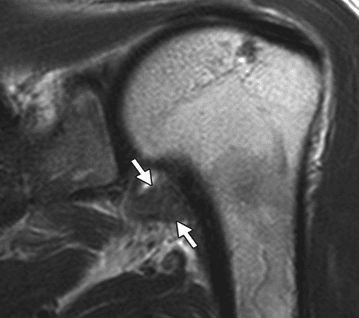

Diagnosticare: Această boală este diagnosticată prin examen clinic, nicio examinare imagistică nu este specifică diagnosticării acestei patologii, deși la examinarea RMN se pot evidenția unele modificări tipice.

Modificări la examinarea RMN, care arată o îngroșare a capsulei articulare.